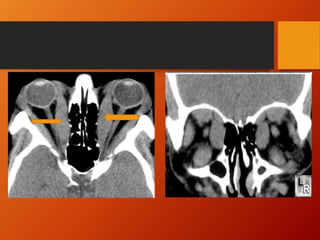

CT Scan and MRI

• CT scan is currently the imaging study of choice.

• MRI is sensitive for showing compression of the optic

nerve.

• Axial and coronal views.

• Neuroimaging usually reveals

 Thick muscle belly with tendon sparing

 Usually IR & MR

 Isolated rectus muscle involvement (SR)- upto 6%

 Bilateral muscle enlargement is the norm

 Unilateral cases usually represent asymmetric

involvement rather than normality of the less involved side